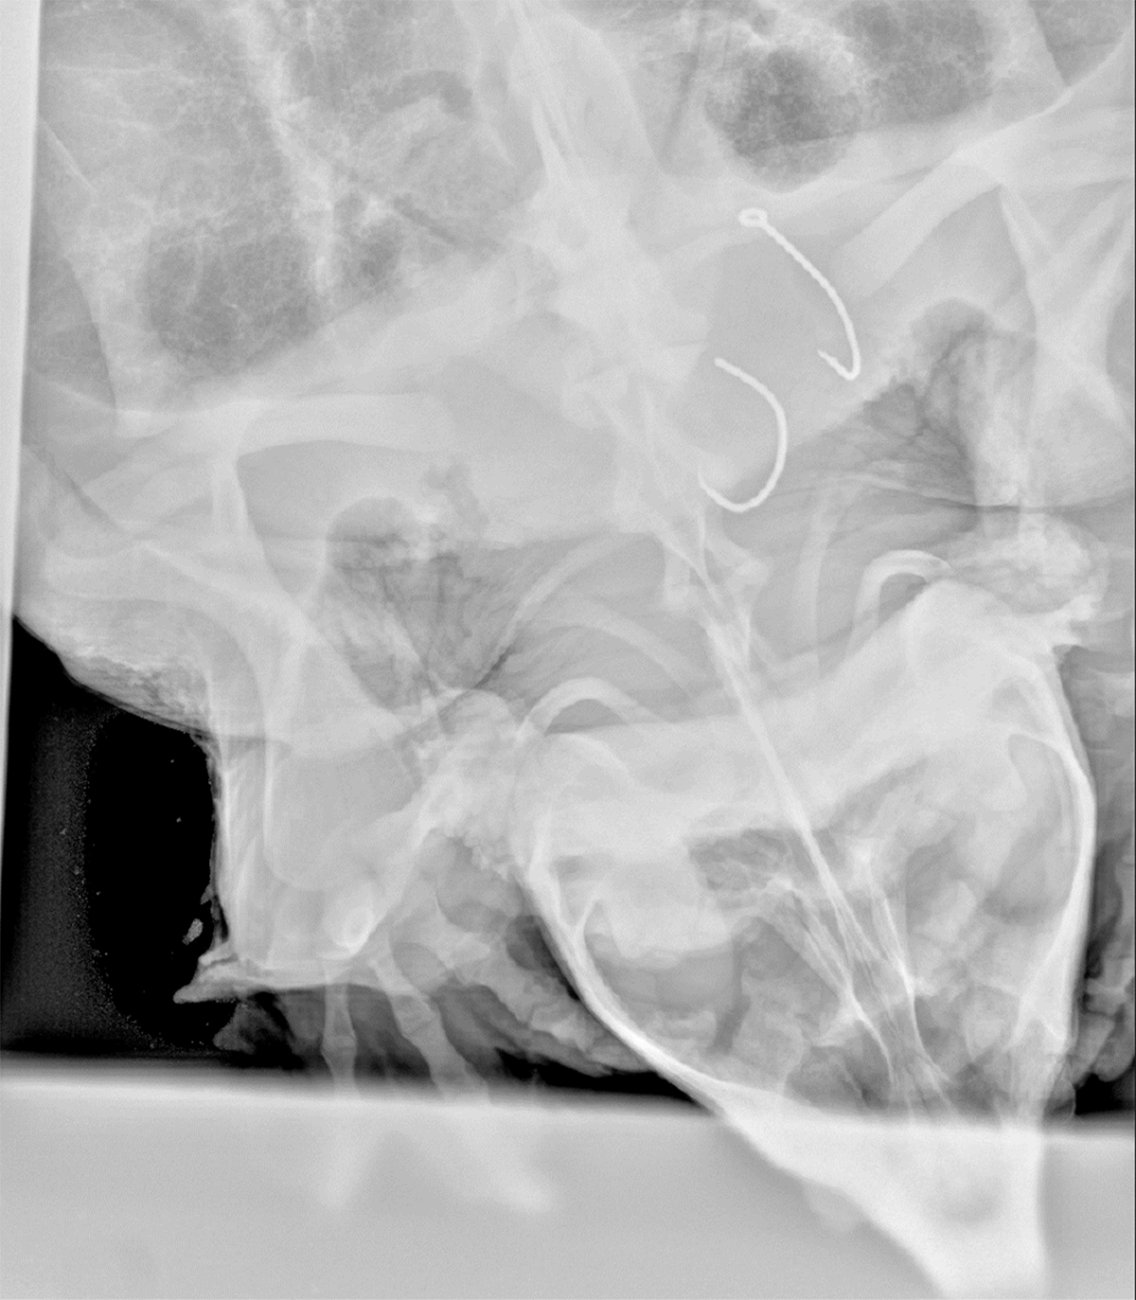

X-ray of alligator snapping turtle shows two hooks swallowed

An x-ray image shows a 75-pound male alligator snapping turtle from the Big Black River, Miss. with two hooks in his throat August 7, 2024. (Photo by Luke Pearson, USFWS)